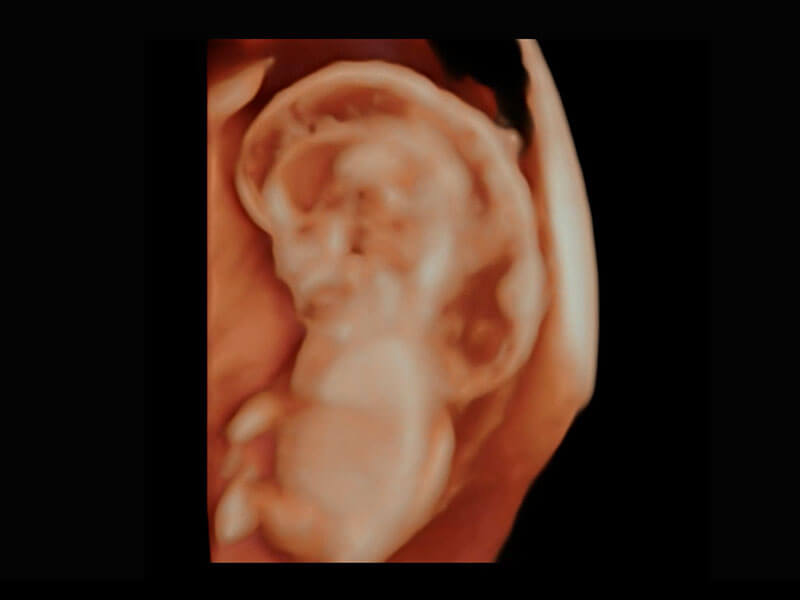

P60提供简单易学易用的高端诊断工具,为您中晚孕筛查提供快速清晰的解剖信息。

S-Fetus能够助您在实时扫查过程中自动识别标准切面、自动测量并录入报告。一个按键,即可快速、高效地获取胎儿生理指标,简化您的产科检查操作。